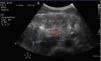

The abdominal ultrasound performed (Fig. 1) revealed the presence of inflammation of the wall of the large intestine (red arrow) with a thickness of 1.45cm (normal value, 0.3cm) and absence of peristalsis seen in the video, compared to the loop of the small intestine (blue arrow), which were findings consistent with colitis (later confirmed by CT scan [Fig. 2]).